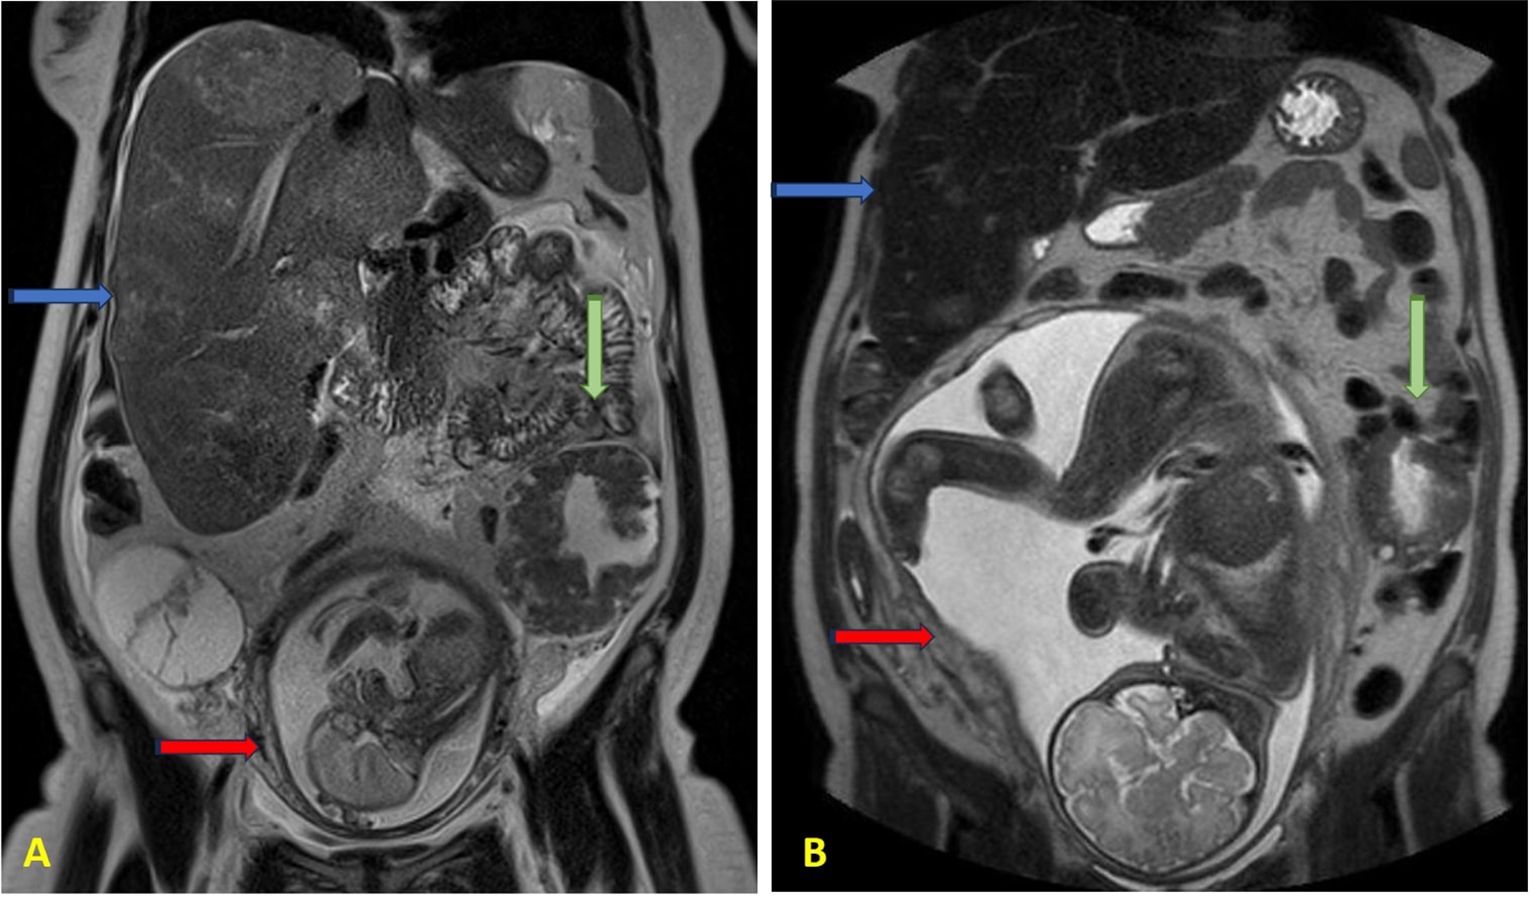

Introduction. Cancer during pregnancy is a rare event and often presents at an advanced stage due to delayed diagnosis. Clinical symptoms are frequently misattributed to normal pregnancy changes, leading to diagnostic challenges. Moreover, concerns regarding fetal safety limit the use of certain imaging modalities and treatment options. Managing cancer in pregnancy requires careful coordination across specialties to balance maternal treatment with fetal preservation. Case-report. We present the case of a pregnant woman diagnosed in the second trimester with advanced metastatic colorectal cancer. The disease involved multiple intra-abdominal sites, and the patient was managed through a multidisciplinary approach. Chemotherapy with FOLFOX scheme was administered during the second and third trimester of pregnancy, leading to a favorable clinical and radiologic response. Delivery was planned at term, with no complications for the newborn. Postpartum oncologic management was continued without delay. Conclusion. This case highlights the importance of individualized care in such complex scenarios and the feasibility and safety of administering chemotherapy during pregnancy.